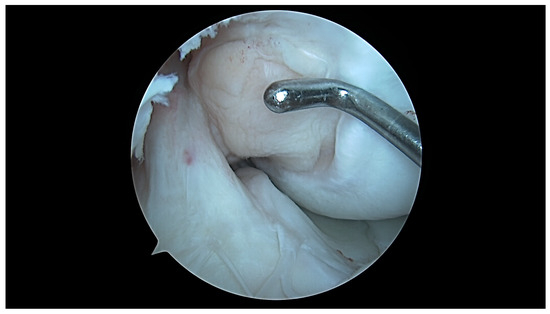

- aICN area: area of the circle defined by three cortical walls of the antero-superior notch (in the custom axial plane/CAP; Figure 3).

- ACL area: area of the closed polygon defined by pointed dots around the cross-section of the anterior cruciate ligament (in the CAP; Figure 4).

- aICN area and ACL area (both appear in Figure 6).